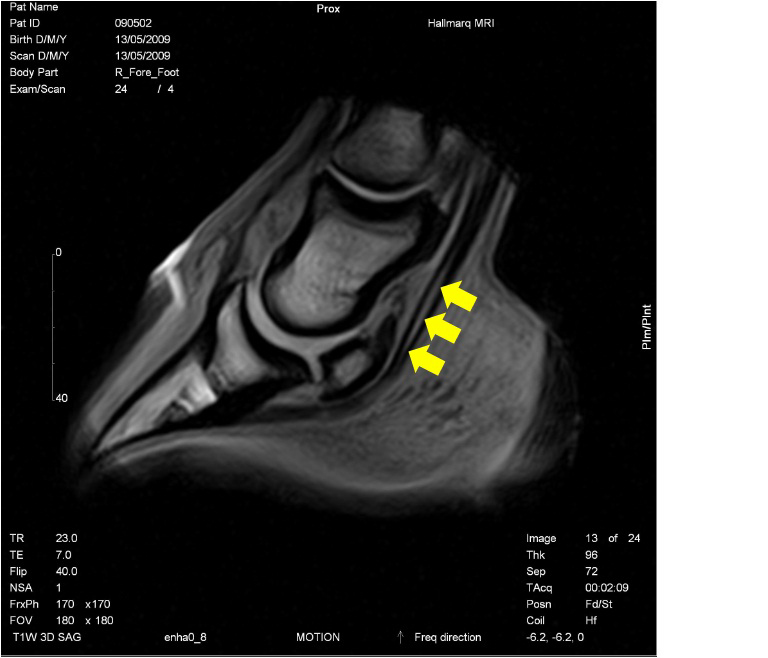

Understanding Navicular Syndrome & Heel Pain in Horses

Fran Jurga`s Hoof Blog: News from Hoofcare + Lameness: Hallmarq …